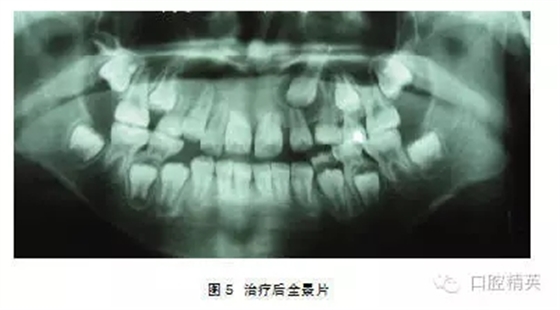

處理:2004年3月行外科開(kāi)窗+正畸牽引治療,7個(gè)月后檢查:1|已萌出,未完全到位,1|唇側(cè)牙根處稍隆起,即為彎曲的牙根。因1|為彎根比較嚴(yán)重,如完全排齊有可能使牙根暴露,故未完全排齊(圖4、5)。

處理:行外科開(kāi)窗+正畸牽引治療,6個(gè)月后破齦萌出,連續(xù)牽引,12個(gè)月后到位(圖5~7)。